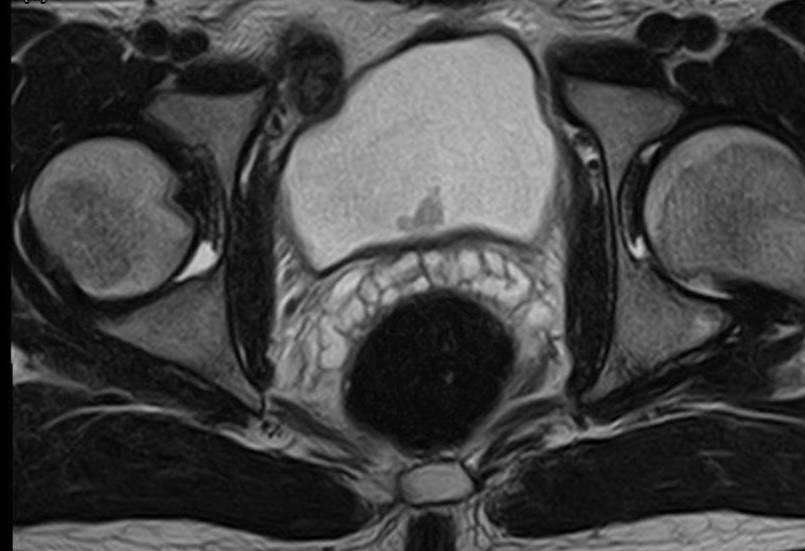

МРТ органов малого таза:

При МР-исследовании органов малого таза с контрастным усилением определяется: Мочевой пузырь слабого наполнения. В области мочепузырного треугольника по задней стенке определяется экзофитное образование размерами 12х5х11 мм, с признаками раннего накопления контрастного препарата и рестрикции диффузии. Признаков распространения процесса на мышечный слой не выявлено. Мочеточники не расширены, устья свободны.